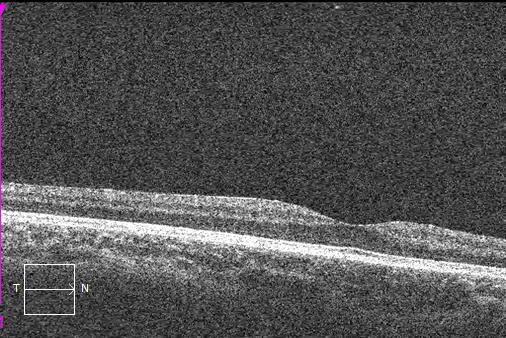

Macular OCT scans and optic nerve head analysis show thin RNFL in both eyes.